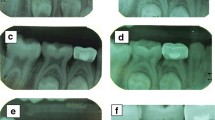

The female patient was born in 1973 and was diagnosed with PNH at the age of 21 in 1994. Since then, she has taken GCs (methylprednisolone, about 24-50 mg/day) for more than 20 years, mostly without interruption although with varying doses. The patient also took ciclosporin for a short time when she was diagnosed with PNH, and she took aspirin and calcium tablets intermittently. In 2011 and 2015, the patient had been hospitalized twice for lower-extremity venous thrombosis. In 2018, the patient experienced spontaneous and nocturnal pain in the upper left posterior teeth, and she visited a general practitioner. Although the toothache symptoms were relieved after pulp access, the general practitioner was unable to access or debride the root canals, and the patient was advised to visit our department. Teeth 25, 26, and 27 had been treated. None of these symptomatic teeth were sensitive to percussion, and testing of their thermal or electrical sensitivity revealed that they did not react. A periapical radiograph showed no obvious root canal image of the symptomatic teeth (Fig. 1a). A diagnosis of pulp necrosis was made for these teeth. The root canals of the symptomatic teeth were examined using cone-beam computed tomography (CBCT) to see whether they were entirely or partly obstructed. The CBCT images revealed that the symptomatic teeth were completely blocked and generalized PCO of the patient’s teeth had occurred (Fig. 1b, c). The patient was in a normal occlusion relationship, with no sign of wear on any of the teeth’s occlusal surfaces (Fig. 2). The patient had no history of trauma or orthodontic or surgical interventions in her teeth or jaws. The symptomatic teeth’s root canals were so obstructed that they could not be accessed or debrided. Then the patient was transferred to another endodontics expert. However, even with the help of an oral surgery microscope and oral ultrasonic equipment, only tooth 26’s mesial buccal and distal buccal canals were accessed and debrided (Fig. 3). Calcium hydroxide was applied to the symptomatic teeth for two weeks, and the AH-plus sealer and gutta-percha were used to obturate the debrided canals, and the unlocated canals went without any further treatment. Then teeth 25 and 27 were filled with composite resin and a crown was made for 25. As for tooth 26, a post–core crown was made. The patient attended a followed-up visit two years later and showed no discomfort or periapical inflammation of the treated teeth (Fig. 4). In 2021, the patient died unexpectedly at the age of 48. The probable cause of death was a pulmonary embolism due to a microthrombus, according to her haematology doctor. Figure 5 shows the entire course of the patient’s diseases.